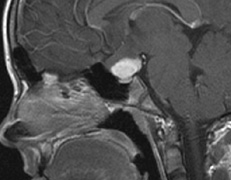

syndrome in 1926. The term von Hippel-Lindau syndrome (VHL) was

first used in 1936.166 The first major clinical criteria for the syndrome were proposed in 1964.167 The main manifestations of von Hippel-Linau syndrome are: histologically similar hemangiomas of the retina and CNS, renal cysts, renal cell carcinomas, pancreatic cysts, pheochromocytomas, and endolymphatic sac tumors.13 EPIDEMIOLOGY The prevalence of VHL syndrome is about 1 in 35,000 to 40,000.168 It is autosomal dominant with greater than 95% penetrance by age 60 years.169 Its expression, even within the same family, may be quite variable, especially for renal disease and pheochromocytoma.170,171 SYSTEMIC FEATURES Cutaneous Findings Cutaneous findings are not part of the diagnostic criteria for VHL syndrome. Neurologic Findings CNS hemangiomas are the most common tumor of VHL, affecting 60% to 80%, with a predilection for the cerebellum and spinal chord. An enlarging cystic component is a frequent finding in symptomatic tumors. Patients typically present in their early 30s; headaches or neck pain in affected individuals should not be ignored.172,173 On microscopy, CNS hemangiomas resemble retinal capillary hemangiomas. Their malignant potential is low.174 The treatment is surgical (Fig. 17, A and B).13 Endolymphatic sac cystadenomas are a sensitive marker of VHL. Patients may present with hearing loss, tinnitus, disequilibrium or facial nerve palsy.175,176 Visceral Findings KIDNEY. Renal cysts are often asymptomatic and do not require treatment. However, complex cysts may carry a risk for malignant transformation. Renal carcinoma affects about a third of patients. Patients typically present in their late 30s. These tumors may be completely asymptomatic, underscoring the necessity for ultrasound screening.13,177 ADRENALS. Pheochromocytomas are benign neural crest tumors of the adrenal medulla (chromaffin cell derived) and probably affect 10% to 20% of patients. Mean age at diagnosis is at about 30 years of age. Pheochromocytomas may be multiple and bilateral. They are catecholamine-secreting tumors that classically produce severe hypertension and anxiety attacks, but they may also be asymptomaic.178 The National Cancer Institute classification of VHL syndrome is in part based on the absence (type I) or presence (type II) of pheochromocytoma (Table 5).171